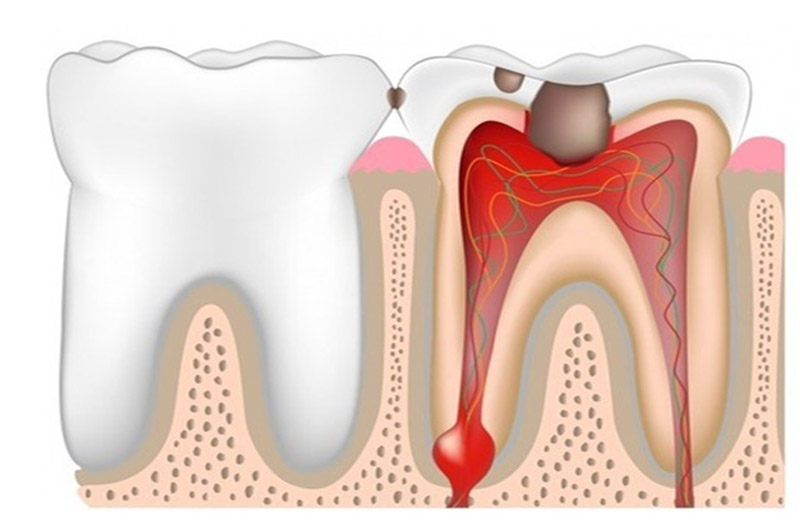

Это наиболее распространенное заболевание зубов. На начальной стадии лечение зубов не составляет особого труда – удаляется больной участок зуба, на его место устанавливается пломба. Cимптомы кариеса: первоначально зуб может немного болеть, либо реагировать на сладкую, горячую или холодную пищу. Со временем боль будет усиливаться. Запущенный кариес может перерасти в острый пульпит.

Пульпит это наиболее запущенная форма кариеса воспаление нерва зуба, которое возникает в результате попадания в корень зуба каких-либо микробов (во время лечения, травмы зуба или запущенном варианте кариеса). Проводится следующее лечение зубов - как правило, удаляется нерв, проводится лечение всех каналов зуба, после чего каналы зуба пломбируются и зуб реставрируется пломбой или коронкой. Удаление нерва, благодаря современной анестезии, совершенно безболезненно. Симптомы пульпита: сильная зубная боль (постоянная или прерывистая), возникающая в ночное время, реакция зуба на горячее.

Образуется она, как правило, у корня зуба, ее рост может приводить к уменьшению здоровой ткани вокруг корня зуба, в результате чего зуб может утратить свою устойчивость и выпасть. Кисту зуба необходимо лечить, а в случае безуспешного лечения - удалять, чтобы предотвратить ее развитие (как правило, хирургическим методом). Киста зуба может также привести к развитию гнойных образований в костной ткани (периоститу). Симптомы кисты зуба: чувствительность зуба при жевании, на надавливание. Пока киста зуба небольших размеров, она никак себя не проявляет, однако при достижении размеров в 3-4 см в диаметре, обнаружить кисту можно за счет видимого отека лица и температуры.